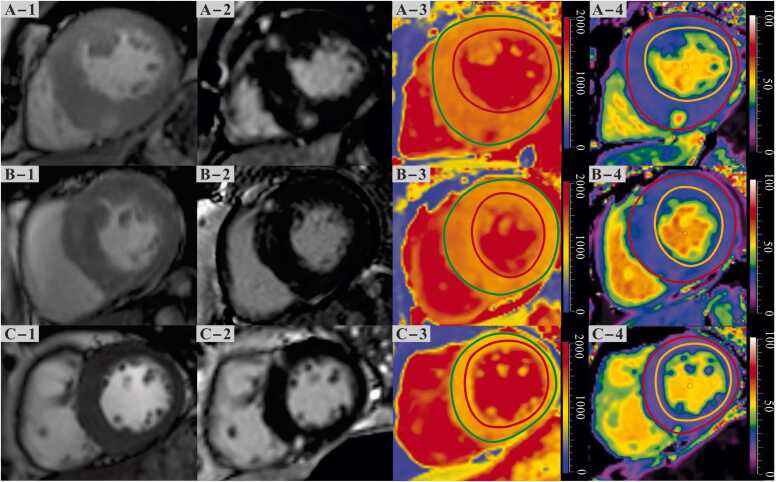

Methods: A total of 737 patients with HCM (99 obese, 298 overweight, and 340 normal-weight patients) who underwent cardiovascular magnetic resonance (CMR) imaging were prospectively included. We assessed the relationship between BMI and LV mass, global native T1, extracellular volume, and late gadolinium enhancement (LGE) using CMR. Myocardial tissues from one patient each with obstructive HCM who underwent septal myectomy of the obese, overweight, and normal-weight groups were obtained and stained with red oil O, hematoxylin, and Masson's trichrome.

Results: LV mass index (87.2, interquartile range [IQR]: 71.3 to 113.8, 89.4, IQR:75.5 to 111.5, and 104.7, IQR: 86.4 to 123.4 g/m2, P < 0.001) was higher in obese and overweight patients with HCM than those with normal weight, but the native T1 was decreased in obese patients with HCM (1324±67 ms, 1308±63 ms, and 1298±67 ms, P < 0.001). In addition, there was no significant difference in LGE extent among the three subgroups (normal weight: 3.7%, IQR: 0 to 9.5%, overweight: 2.7%, IQR: 0 to 7.7%, obese: 3.8%, IQR: 0 to 7.2%, P = 0.194). Multivariable linear regression analyses found that BMI was independently associated with global native T1 (β = -1.918, P = 0.005). Furthermore, myocardial tissues stained with oil red O from three patients showed an increasing extent of fat deposits with BMI, whereas collagen volume fractions were similar.